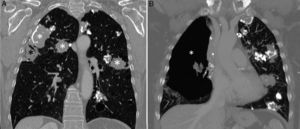

We report the case of a 66-year-old woman with a history of nodular primary pulmonary amyloidosis, not receiving treatment as she was practically asymptomatic. A follow-up chest CT showed, in addition to already known multiple nodules and pulmonary masses, a subpleural cavitating lesion in the right lung (Fig. 1A), with a loculated pneumothorax in the same side (Fig. 1B). Given the lack of symptoms, we decided to manage the pneumothorax conservatively.

(A) Coronal reconstruction of chest CT (pulmonary parenchymal window) showing multiple nodules in both lungs (white asterisks). Note a subpleural cavitating lesion in the right lung (black asterisk). (B) Coronal reconstruction of chest CT (pulmonary parenchyma window, more anterior plane than image A), showing anterior loculated pneumothorax in right hemithorax (asterisk).